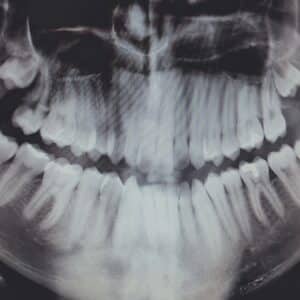

Does Medicare Cover Cosmetic Dental Procedures for Reconstructive Purposes After an Accident?

Navigating the complexities of Medicare can be daunting, especially when it comes to understanding what dental procedures are covered. Medicare, primarily designed for individuals aged 65 and older, offers limited…